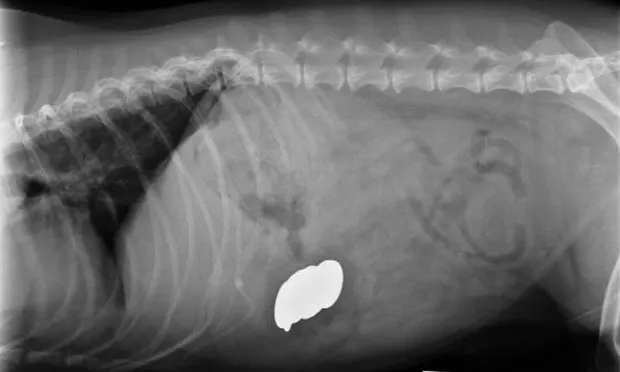

Abdominal radiography revealed metallic foreign bodies (Figure 2) in the stomach. Multiple coins, including some zinc containing pennies minted after 1982, and a medallion were removed endoscopically (Figure 3). Blood zinc levels were not measured.

Lateral abdominal radiograph revealing metallic foreign bodies